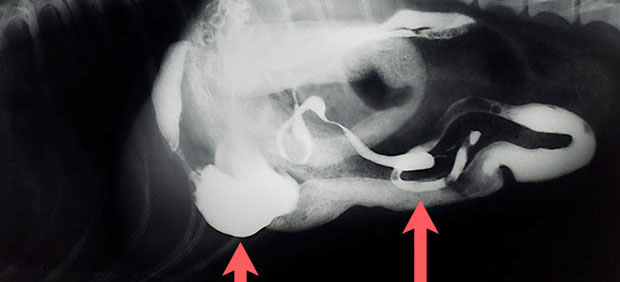

Kontrastmittelaufnahme des Magen-Darm-Traktes